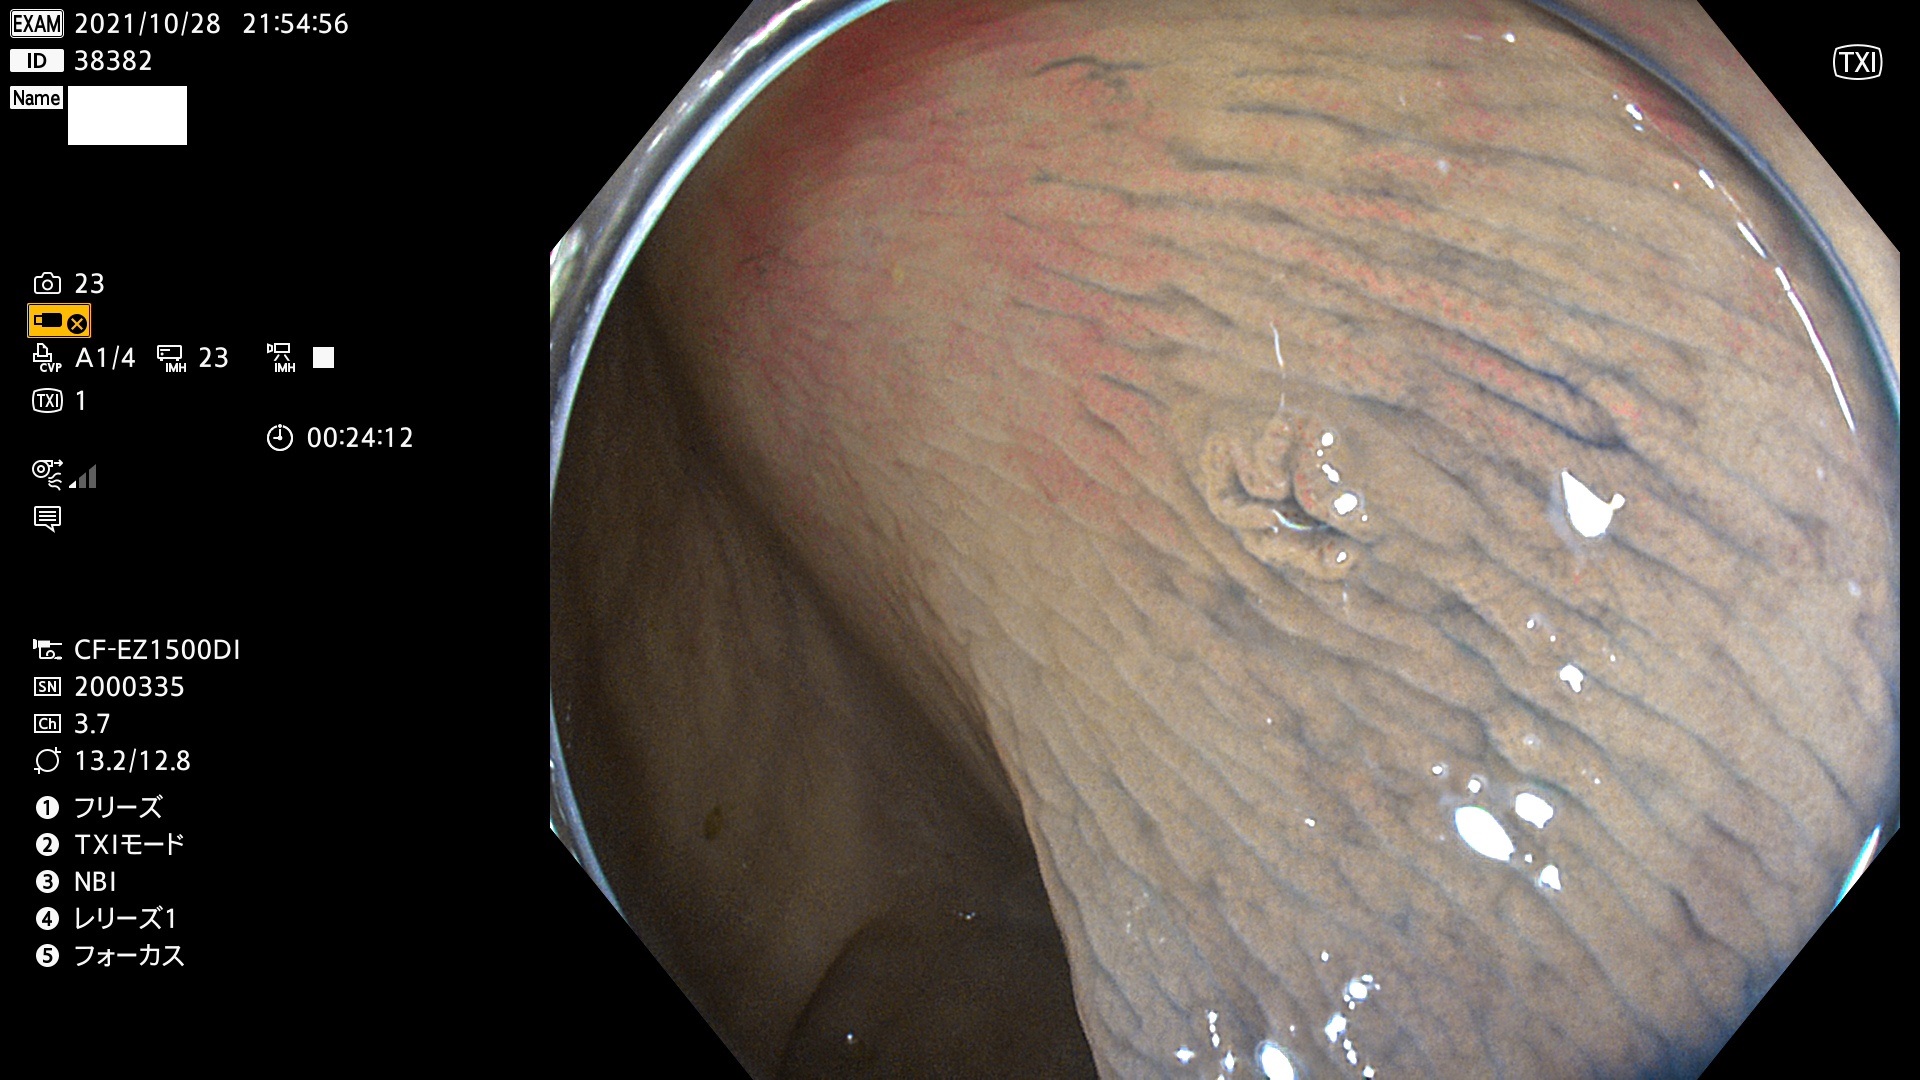

38300 38301 38302 38303 38304 38306 38307 38308 38309 38310 38311 38312 38313 38314 38315 38316 38317 38319 38321 38322 38323 38324 38325 38327 38331 38332 38333 38334 38337 38338 38339 38340 38341 38343 38346 38348 38349 38350 38351 38352 38353 38354 38355 38358 38359 38360 38361 38362 38363 38365 38366(SSAP) 38368 38369 38370 38371(SSAP) 38372 38374 38375 38376 38377 38378 38380 38381 38382 38383 38384 38385 38386 38388 38389 38391(SSAP) 38395 38397 38399

発見困難で危険性の高い平坦型病変(上記100名より抽出)